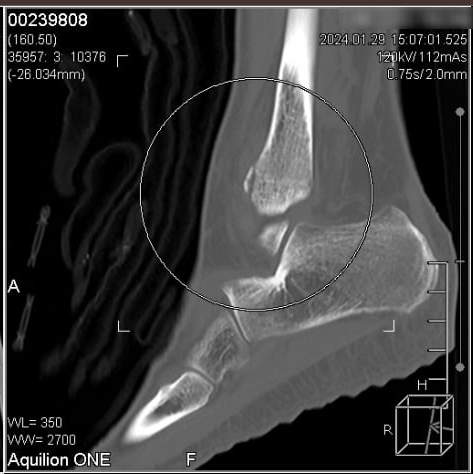

안녕하세요 ​한의초음파연구회 학술이사문지현 원장입니다​​ 엑스레이상인대가 늘어났다고 했는데...​속시원히 진단해주셔서 감사합니다 CT상 발목 골절로 진단 ​양천구에서 교통사고 후​발목통증으로 입원했던 환자분께서​제게 하신 말씀입니다.​​​교통사고 후에​발목 치료를 받아도안 낫는 분들은 ​이 글을 끝까지 읽어보셔서시간낭비하는 일이 없기를 바랍니다.​​ ​저는